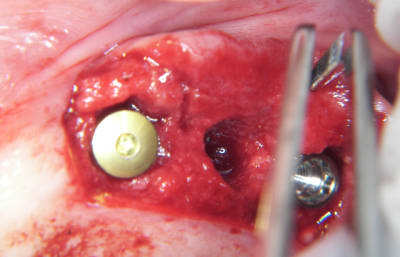

Tu veux dire une crête comme ça?

--

xbk

"Si tous ceux qui croient avoir raison n'avaient pas tort, la vérité ne serait pas loin" Dac Pierre